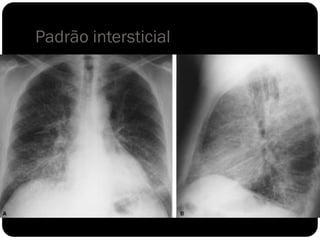

Padrão intersticial

 O interstício pulmonar é todo o tecido conjuntivo de

sustentação que mantém a arquitetura alveolar. Os vasos,

brônquios e linfáticos situam-se no interstício.

 Infiltrações intersticiais parenquimatosas podem aparecer na

forma de padrão

reticular

micronodular

reticulonodular.

 Sinônimo de espessamento septal: Linha de Kerley